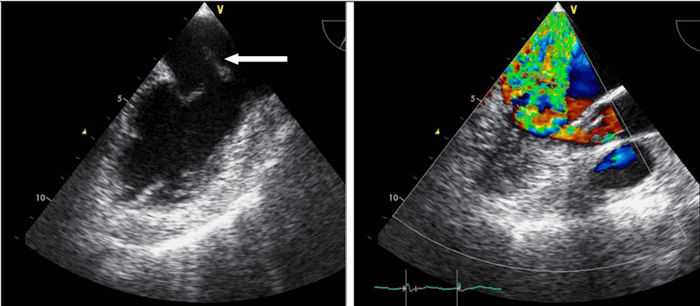

Для облегчения выявления турбулентного движения (завихрений) существует порог скорости, выше которого происходит изменение цвета (во многих аппаратах это зелены). «Мозаичный» узор на участке турбулентного потока позволяет легко установить регургитацию (смену направления движения), что помогает определить степень недостаточности клапанов.

Цветовой допплер (Color Doppler). Цветовой допплер - аналог импульсного допплера, где направление и скорость кровотока картируется различным цветом. Так кровоток к датчику принято картировать красным цветом, от датчика - синим цветом. Турбулентный кровоток картируется сине-зелено-желтым цветом.